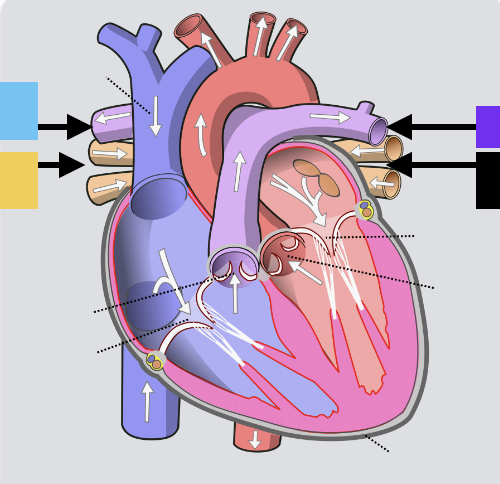

aortic valve

pulmonary valve

tricuspid valve (right AV)

bicuspid valve (left AV)

chordae tendineae

papillary m.

trabeculae carneae - only in ventricles

pectinate m. - only in R atrium

fossa ovalis

opening of coronary sinus

parietal pericardium

visceral pericardium (connective tissue) / epicardium (muscle)

myocardium

endocardium

superior vena cava

inferior vena cava

pulmonary trunk

left pulmonary artery

left pulmonary veins

(branches of) right pulmonary artery

right pulmonary veins

ascending aorta